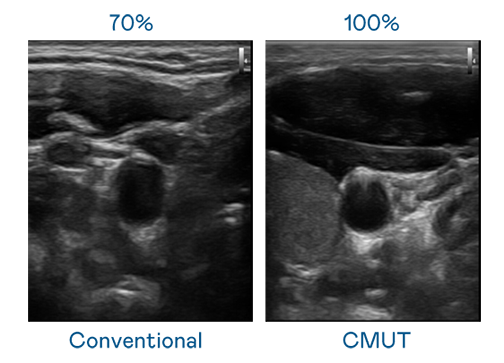

CMUT 技术是一种用电容式微机电元件来产生超音波讯号的技术。与传统 PZT 压电式技术相比,CMUT 频宽增加 30%,更宽频的超音波讯号让影像解析度大幅提升,是实现高影像品质医疗超音波扫描、促进精准医疗发展的关键技术。

大频宽带来超清晰影像

超音波影像的解析度高低,首先取决于探头能发出的讯号频宽。AG庄闲 CMUT 可提供高清晰的超音波讯号,提供高频宽、高灵敏度、影像纹理细节更高的超音波影像,协助医护人员缩短影像判读时间及利用精准的医疗影像进行诊断。